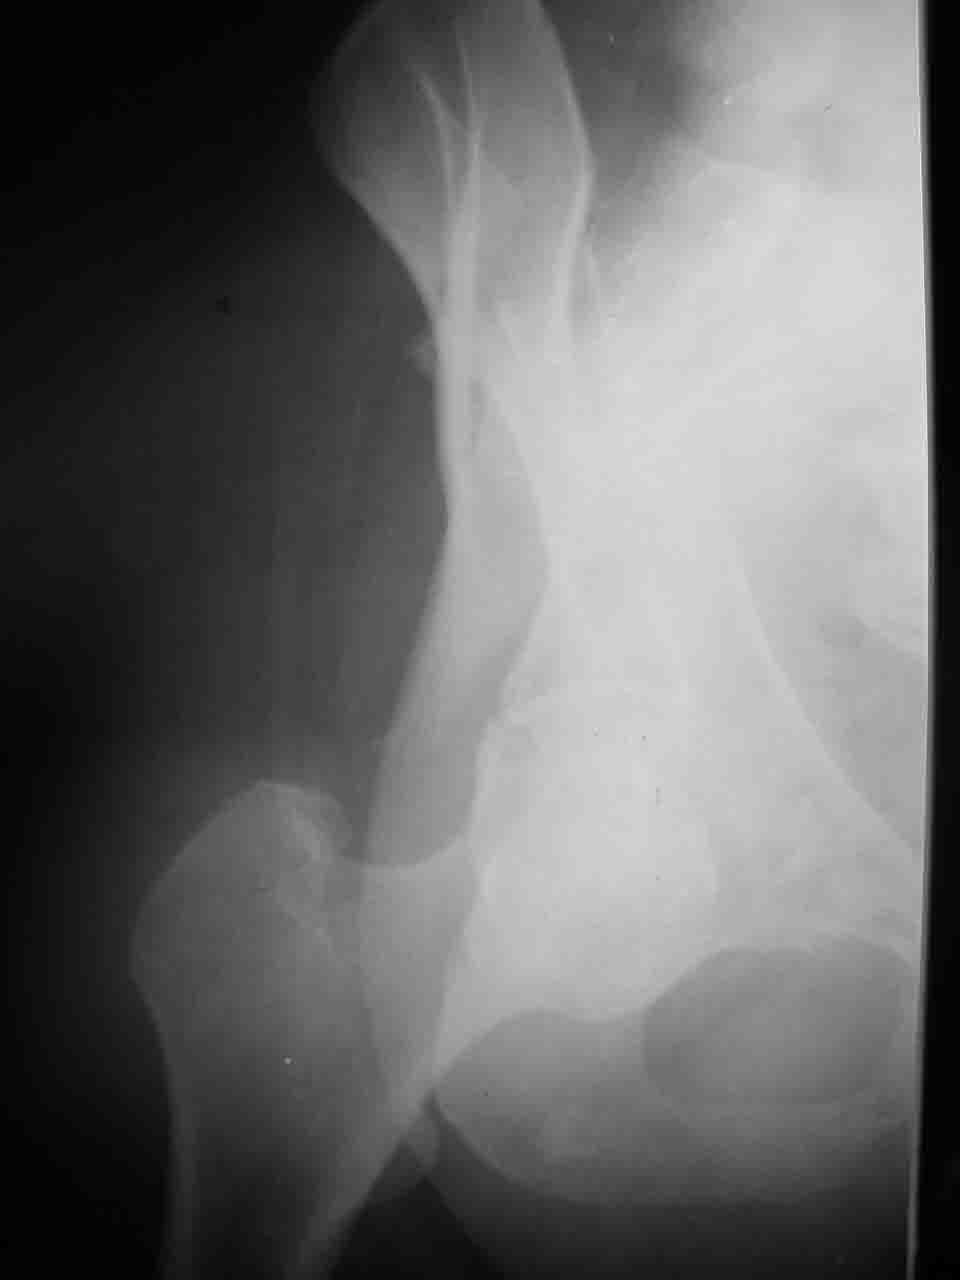

А какой отдел вертлужной впадины более важен передний или задний? Чем был обусловлен выбор доступа к суставу? Проще говоря, почему вы пошли передним доступом на двухколонный перелом? Мне понятны ваши сомнения, когда не удется сделать все что хотелось бы. В данном случае доступ должен быть чрезвертельным боковым (как и советовал Рунков) или двумя доступами.

Интерес к реконструкции вертлужной впадины у меня появился довольно-таки давно, но до недавнего времени как-то не ощущалась готовность к практической реализации, а местный подход достаточно консервативен - перелом срастется,

а далее будет видно. Такую точку зрения я не разделяю, поэтому через конференции,ортофорум и свои случаи пытаюсь практически и теоретически *продвинуть* для себя тему реконструкции вертлужной впадины.

Логика подсказывает, что все-таки лучше иметь анатомически полноценную впадину, хотя ранее упоминалось состояние вторичной конгруэнтности и одно наблюдение у меня есть, когда у больного с полностью нарушенной анатомией впадины и подвывихом головки бедра кзади и кверху боли отсутствовали при относительно достаточном для стиля жизни больного объёме движений. Но это только одно наблюдение и кроме перелома впадины у этогобольного была и тяжелая ЧМТ в анамнезе. Основываясь на формулировке структуры ацетабулюм Э. Летурнеля - как перевернутой буквы Y, впадина для полноценной функции сустава должна иметь сферичность, соответствующую размеру головки бедра и если один из компонентов в дефиците, то функциональные последствия рано или поздно проявятся.

Сложностью, ассоциативностью характера перелома, я бы с радостью воспользовался мининвазивной перкутанной фиксацией винтами, но боюсь, что результат был бы ещё хуже, техникой непрямой репозиции перелома не владею, поэтому пытаясь получить анатомичную впадину приходится широко открывать, по крайней мере пока, а дальше буду пытаться уменьшать пространство...

Илеофеморальный доступ не совсем передний и сравнительно с илеоингвинальным, и Кохера-Лангенбека открывает весь наружный таз кроме самых передних отделов лонных костей, фиксацию которых я не ставил в задачу. Обширность диссекции, большая длительность операции и более высокий риск гетерооссификации - отрицательные моменты в обмен на возможность легче ориентироваться.

Вопрос доступа к вертлужной впадине при остеосинтезе задача не простая. Конечно, у Летурнеля и Тайла всё давно описано, нам остается только брать на вооружение. Но сами понимаете, что не бывает двух одинаковых ситуаций, поэтому в каждом случае вопрос решается сугубо индивидуально. Наша главная цель - восстановить анатомию с нанесением минимальной дополнительной травмы тазобедреннному суставу, думаю с этим никто не поспорит. Расширенный илиофеморальный доступ уж слишком травматичен (как сказал один коллега "таз лежит отдельно, больной отдельно").Стоит ли делать из пациента анатомический препарат для того чтобы легче ориентироваться. Да и нужно ли собирать всю "мозаику"? Мы применяли при таких операциях своеобразную операционную хитрость - сначала устраняли грубое смещение крыла под гребнем с фиксацией так называемой "плавающей" пластиной (временно фиксированной на двух винтах)- доступ или продлевали боковой, или делали небольшой дополнительный разрез над гребнем. Это позволяло устранить грубое смещение и захождение отломков тела повздошной кости, что значительно облегчало репозицию и остеосинтез впадины над сводом. Основное внимание конечно же уделяли нагружаемому задне-верхнему отделу. Сообщите ваш адрес, пришлю схемы и рентгенограммы.